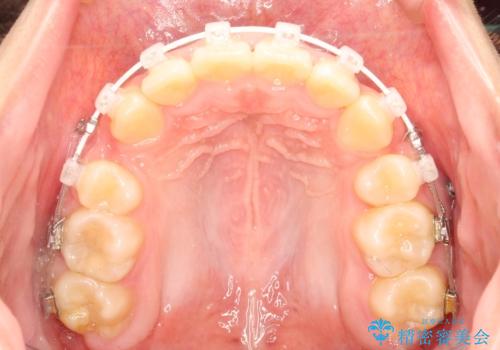

- 矯正装置

- 審美装置

- 上下左右4本の小臼歯を抜歯、ラビアル・ワイヤー矯正を計画した。

抜歯をして第1小臼歯分のスペースを獲得することにより、ガタつきの改善と前歯のリトラクトをおこない、横顔の印象もすっきりとし、整ったEラインを作ることができました。